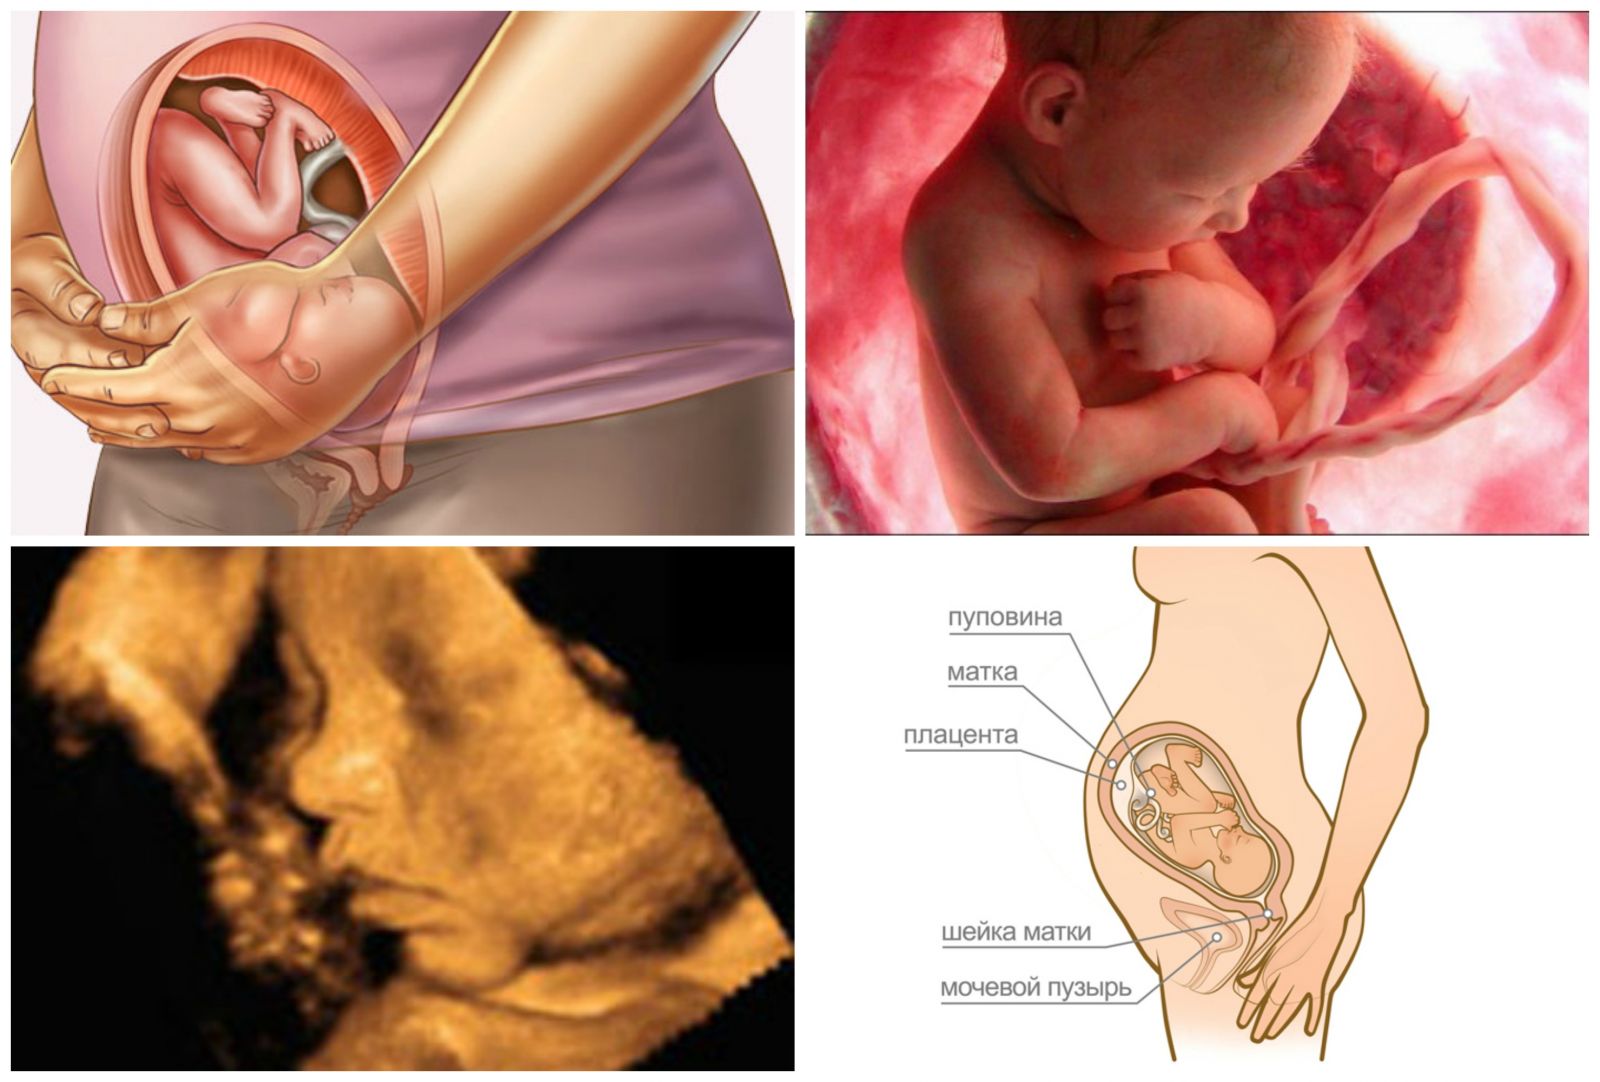

37 неделя какой срок

37 неделя какой срок 142 фото